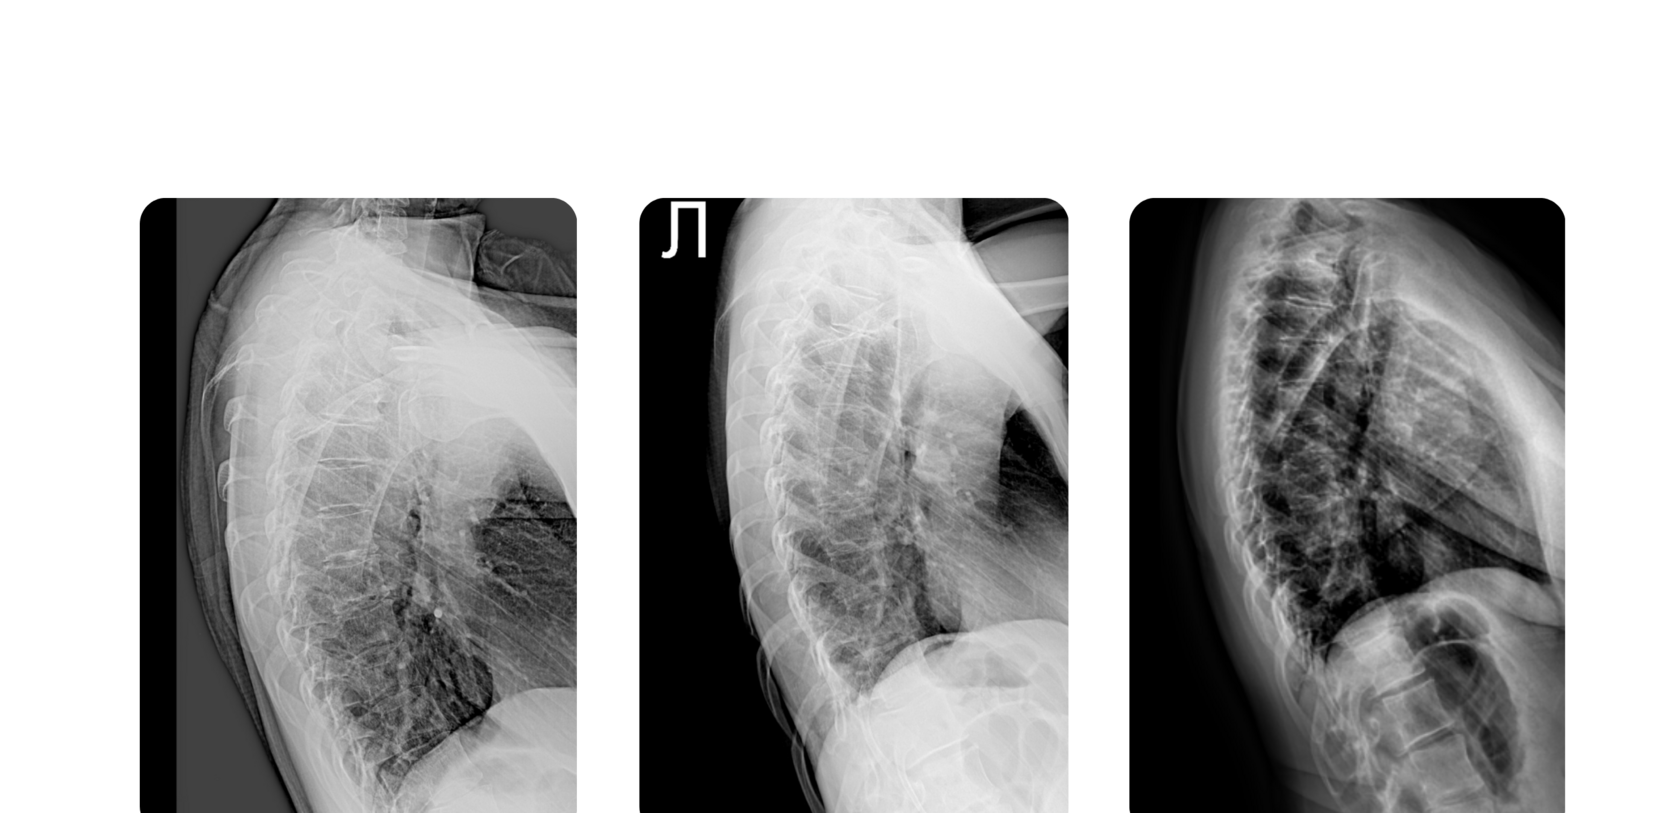

ДЗ: рентген-снимки и заключения "ДО"

ДЗ: рентген-снимки и заключения "ПОСЛЕ"